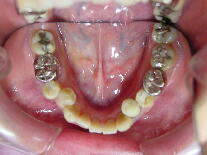

症例3 (30代 女性) 右下顎切歯先天性欠如

左右上顎第一小臼歯・右下顎第一小臼歯抜歯例

![]() ![]() ![]()

初診から1年3ヶ月後